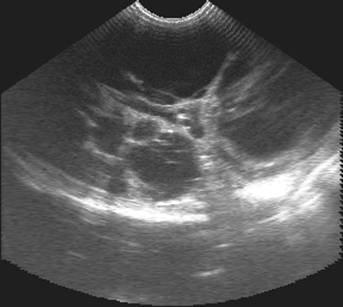

Полікистоз нирок

Назва - полікистоз нирок - дає уяву

про його сутність і дослівно перекладається як наявність множинних порожнин в

структурі нирки. Полікистоз нирок є аутосомально домінантним спадковим

захворюванням.

Рис.3. Полікистоз правої кирки кота

4 років, фрагменти сканограм

Розміри кист можуть коливатися від 1

мм до 1 см і більше. З віком їх розмір і кількість збільщуються аж до повного

заміщення нормальної структури нирки різнокаліберними порожнинами. Досить часто

аналогічні кисти можливо виявити в ураженої полікистозом тварини і в інших

органах - підшлунковій залозі, печінці, матці. По мірі прогресування

захворювання і порушення нормальної структури нирок не може не знизитися їх

функція. Зниження функції нирок характеризується хронічною нирковою

недостатністю, що, як правило, є першим тривожним симптомом цього захворювання.

В теперішній час завдяки можливостям

ультразвукового дослідження органів діагностика полікистозу нирок реальна на

самих ранніх етапах захворювання. Дослідження повинно проводитися

кваліфікованим спеціалістом, тому що кісти на раніх стадіях досить маленькі -

1-3 мм. У більш пізньому віці їх легше спостерігати за допомогою УЗД. На основі

проведених досліджень ветеринарні спеціалісти прийшли до висновку, що

найнадійнішим і високорезультативним буде проведення досліджень у віці 10

місяців. Розміри тварини і її органів практично відповідають дорослим нормам,

що дозволяє простіше виявити всі можливі відхилення. При полікистозі значна кількість

ехонегативних структур різних розмірів і форми спостерігається протягом всієї

ниркової паренхими.